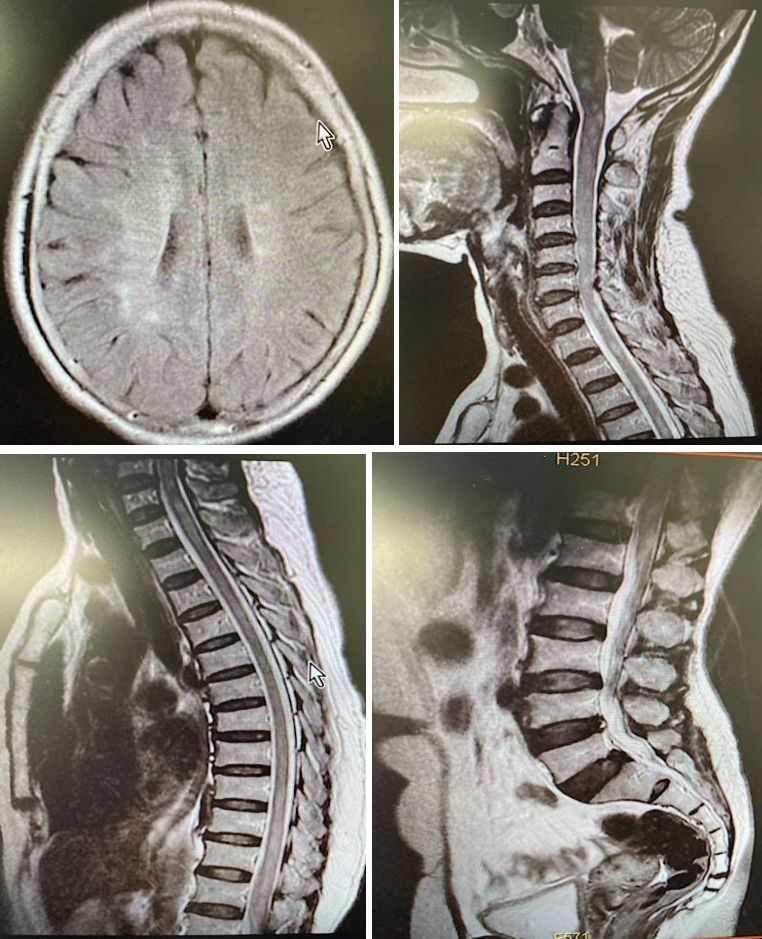

女,51岁,双下肢麻木、行走欠稳1月余,肌力5-级,双上肢正常,大小便障碍。

答案:抗Hu抗体相关副肿瘤综合征。补充检查:抗Hu抗体阳性,胸部CT可见一个小结节存在,余无异常。中年女性患者,亚急性起病,双下肢麻木、行走不稳,肌力有减退,二便障碍。影像学见双侧半卵圆中心、脑干及脊髓长节段病变。结合病史、查体及影像考虑脱髓鞘、免疫及肿瘤代谢性疾病。患者CSF白细胞280,一般实验室检查无异常排除感染。好多老师看到了脑室旁髓静脉样条纹,考虑为自身免疫性GFAP星形细胞病。该病早期称为慢性或亚急性激素反应性非血管炎性自身免疫炎症性脑膜脑炎。病程也有类似,通常40岁女性以上易发,急性或亚急性起病,呈进行性加重或复发-缓解病程,临床表现多样,包括发热头痛,脑病,脊髓炎,视力异常,锥体外系症状,共济失调,自主神经功能障碍等。但是该病CSF检查白细胞数增多,蛋白升高,寡克隆区带阳性。脑脊液和血清中检测到GFAP抗体可确诊。影像特征性表现为垂直于脑室的脑白质血管周围线样放射状增强。

还有多数老师考虑脱髓鞘病,CSF蛋白较高,余正常,影像表现也不符合脱髓鞘病的特点,亦排除脱髓鞘疾病。对于脊髓病变,诊断思路如下: